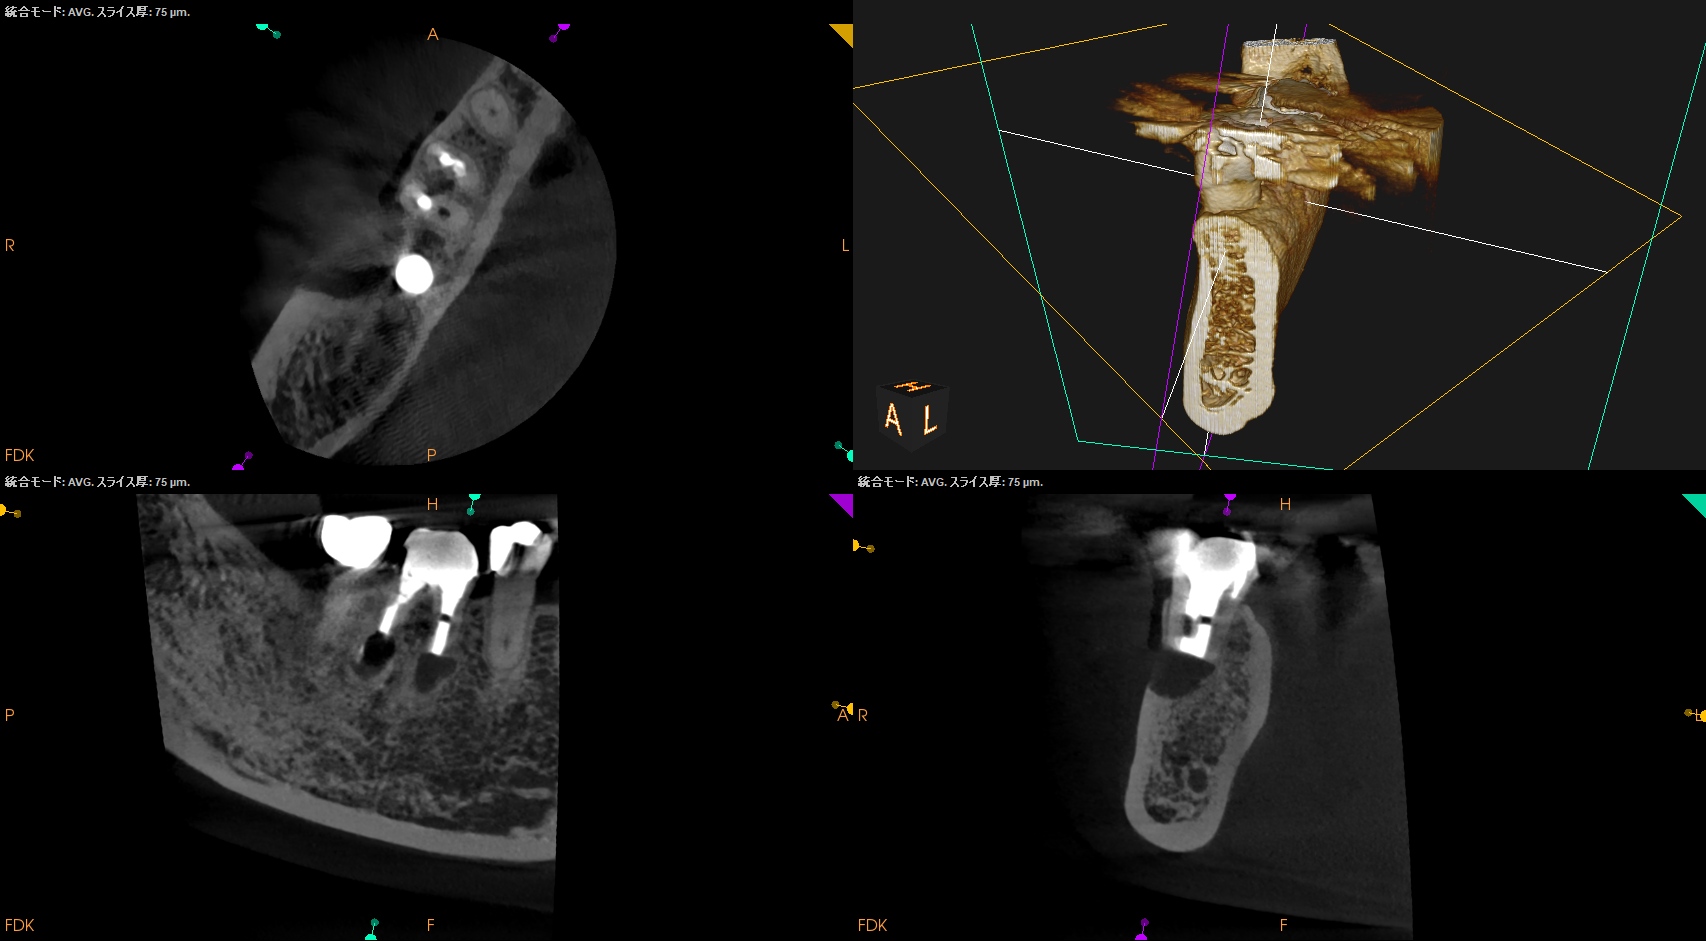

CBCT(2025.10.27)

MB

ML

DB

DL

MのApexに到達するにはCEJよりも12.5mm下方の歯槽骨を2mm削合(Osteotomy)しなければならない。

Apexを見つけたら3mm切断するがこの時の頬舌的な幅径が6.3mmだ。

リンデマンバーの半分よりも長い。

またDはApexに到達するには、CEJよりも13mm下方の歯槽骨を3mm削合する必要がある。

MのApexの位置を予想し、Osteotomyしていく。

その際の深さは

2mmである。

クラウンのマージン部よりも13mm下方にDのApexがある。

そこに行き着くには歯槽骨を3mm削合する必要がある。

術後にPA, CBCTを撮影した。

気泡はあるが問題はないとして縫合した。